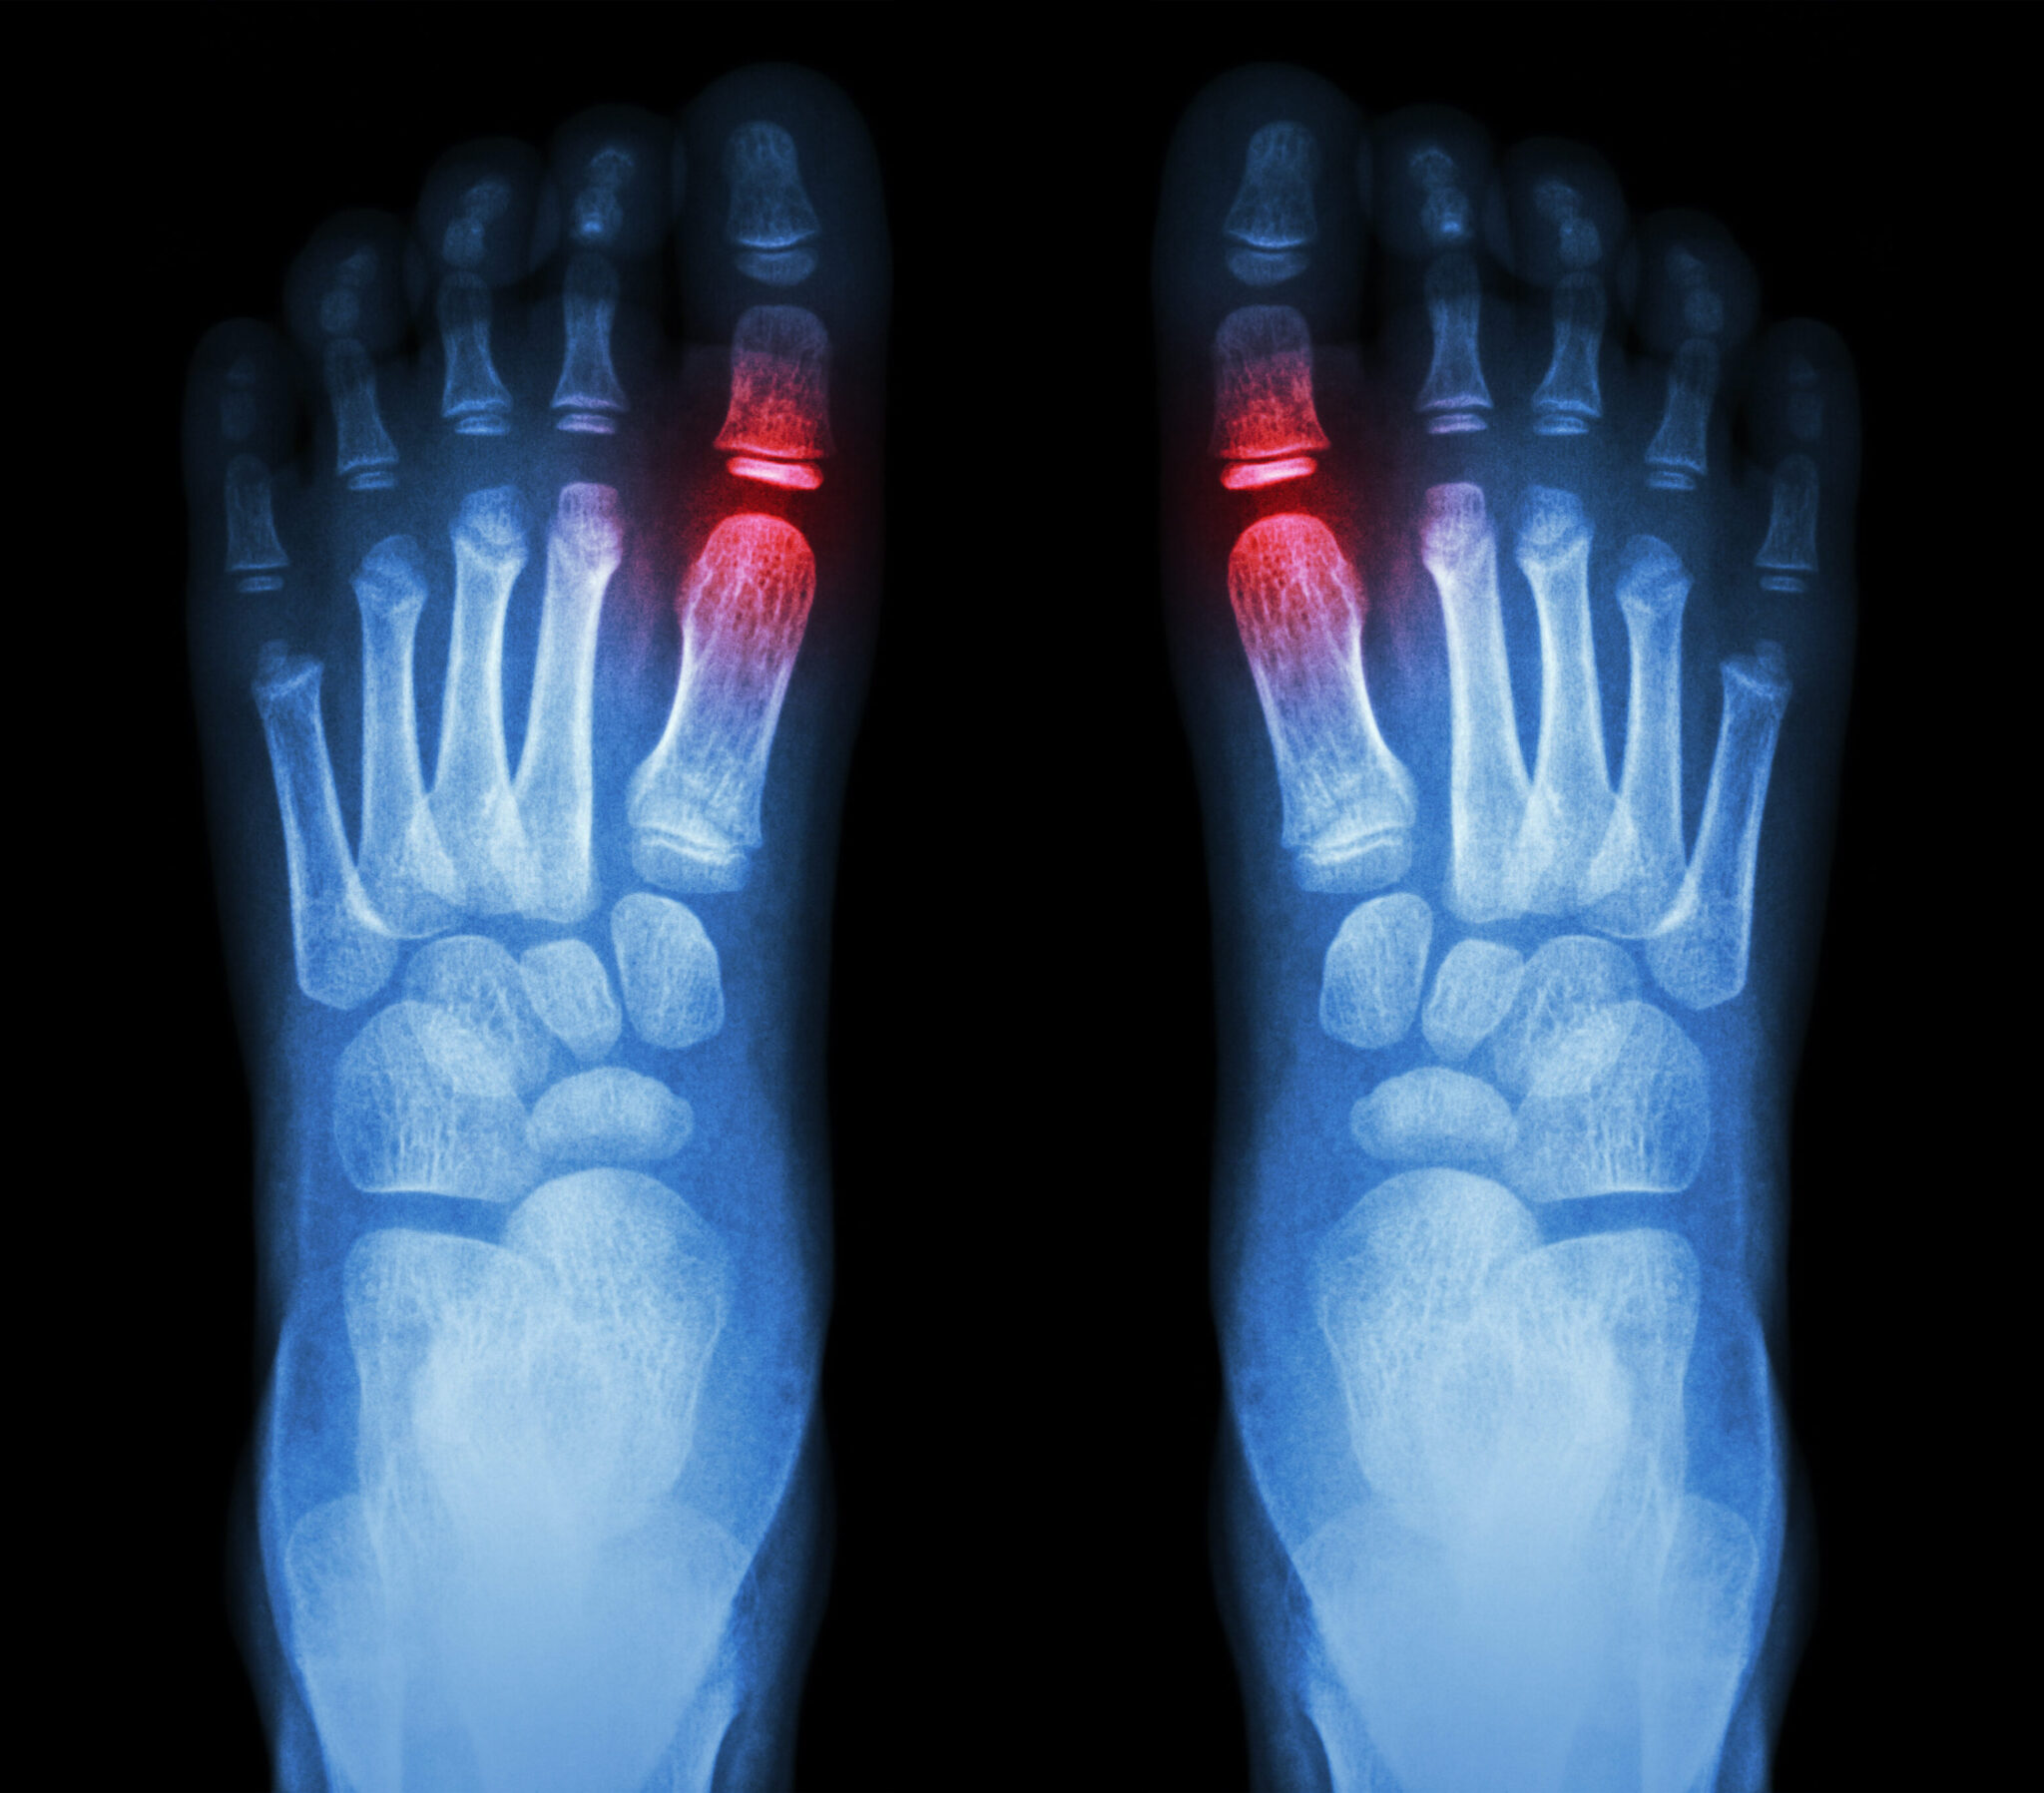

What Does Shooting Pain In Toes Mean .   understanding toe pain. The sensation of an electric shock in these areas;  sharp foot pain can manifest in various ways, from a sudden stabbing foot pain sensation to a persistent burning or tingling. Pain that usually worsens at. Big toe pain has a wide range of possible causes. It may be a little irritating or so debilitating that you cannot put any kind of pressure.   tingling, burning, sharp, or shooting pain in the toes or feet;   what does pain in the big toe indicate? The first step towards finding relief. If you’ve ever stubbed your toe walking to the bathroom in the dark then you understand that for something so tiny, a toe.   toe pain is any uncomfortable sensation in the toes.